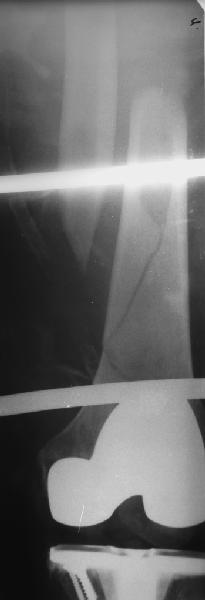

В приложении - недавний перипротезный перелом.

----------- следущая часть -----------

Вложение не в текстовом формате было извлечено&hellip;

Имя     : 3get_image.jpg

Тип     : image/jpeg

Размер  : 9627 байтов

Описание: отсутствует

Url     : http://weborto.net:8080/pipermail/ortho/attachments/20110903/40f50831/attachment-0008.jpg